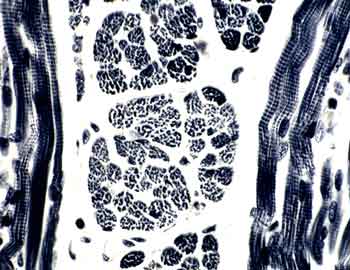

Od-10 Intestino delgado (Hematoxilina-eosina)

Visión general: Se ha seleccionado una sección de la pared del intestino delgado para mostrar diferentes formas de presentarse las células musculares lisas. A pocos aumentos nos permite observar las vellosidades intestinales como evaginaciones de la mucosa revestidas por un epitelio en el que destacan las células absortivas, y entre ellas las glándulas tubulares rectas que se introducen en profundidad y que ya estudiábamos en la práctica de epitelios. Por debajo de esta capa mucosa, aparece la submucosa y por fuera una capa muscular bien desarrollada responsable del peristaltismo intestinal.

Visión específica: Cuando a mayores aumentos pasamos a buscar células musculares lisas, hemos de detenernos en tres zonas diferentes. Primero en la propia vellosidad intestinal, en cuyo eje conjuntivo aparecen, junto con el quilífero central, algunas células de esta naturaleza que constituyen el músculo de Brücke; las observamos preferentemente cortadas en sentido longitudinal y aparecen como elementos alargados de núcleo único y central. Posteriormente y, tras repasar la ya conocida arquitectura de las glándulas, llegamos a su límite inferior en donde una fina capa muscular lisa marca el paso a la submucosa; se conoce como capa muscular de la mucosa. Tras pasar por la capa conjuntiva submucosa llegamos a una doble capa de células musculares que las vemos cortadas tanto en sentido longitudinal como transversal constituyendo gruesas túnicas.